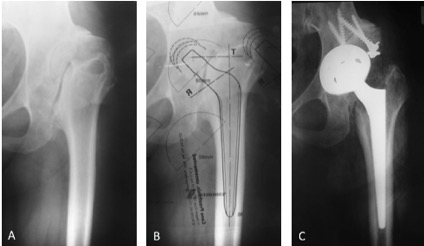

Uso de copas de tantalio trabecular para la reconstrucción acetabular compleja. Resultados de una serie de 42 casos y un seguimiento promedio de tres años.[Trabecular metal cup outcomes in complex acetabular reconstruction. Review of 42 cases with a 3-year follow-up].